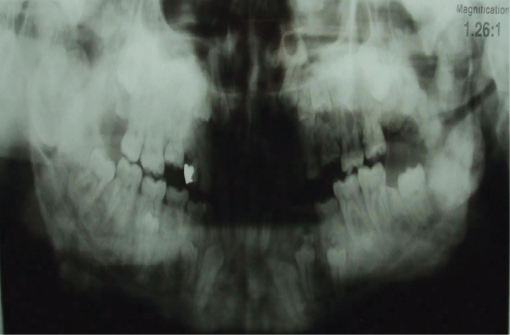

Figure 3.

Case 1 panoramic radiography.

A 21-year-old male patient, one of two siblings, presented to our department with dental deficiencies, chewing and aesthetic concerns and asymmetry that had newly emerged in his face. Anamnesis taken from the patient established that his mother and sister had been diagnosed with Gardner syndrome. Severe asymmetry in the mandible was observed at extraoral examination. At intraoral examination, we determined an Angle Class I molar relationship, and we observed that a large number of permanent tooth eruptions had not been completed in the anterior and posterior regions. No anomaly was observed in any intraoral soft tissue (Figures 1 and 2). At radiological examination, congenital deficiency in the right and left upper central teeth, delayed eruption in the maxillary and mandibular canines and 1st and 2nd premolars and supernumerary teeth were observed. There was an increase in density in the structure of the bony trabecular and smooth-nerve radiological formations in the right condyle region and right and left lower jaw angulus region (Figures 3 and 4).